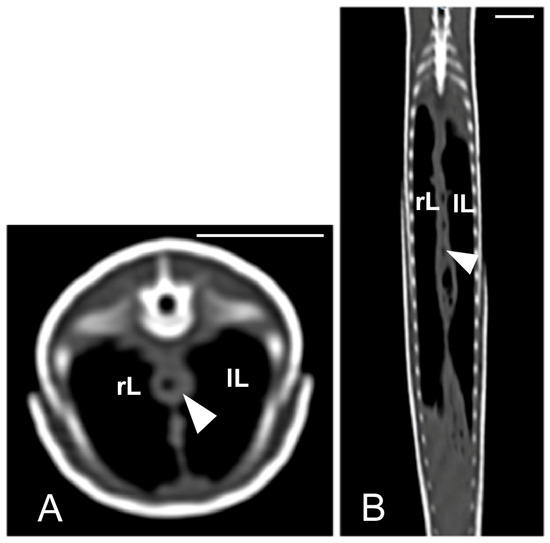

The cloaca was identified in the caudoventral part of the coelom in only two animals due to the presence of hyperattenuating content in the lumen (urate salts) (Figure 15).

Figure 15.

The CT images of Pseudopus apodus in the transverse (A), sagittal (B), and dorsal (C) planes showing hyperattenuating content (urate salts) (arrows) in the cloaca. Bar = 10 mm.